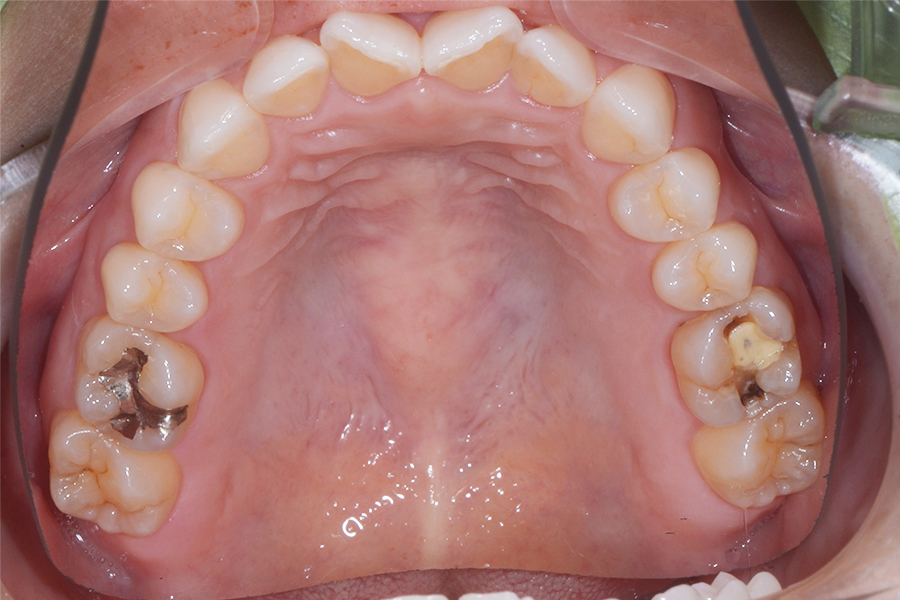

【40代女性】

真ん中二本の捻じれた歯を

治したい

• 治療前

主訴 真ん中二本の捻じれた歯を治したい

期間 治療期間8か月

費用 治療費35万(別途調整料)

※デンタルローン120回 ¥3,300/月

治療内容 上顎リンガル矯正(裏側矯正)

治療に伴うリスク 後戻り